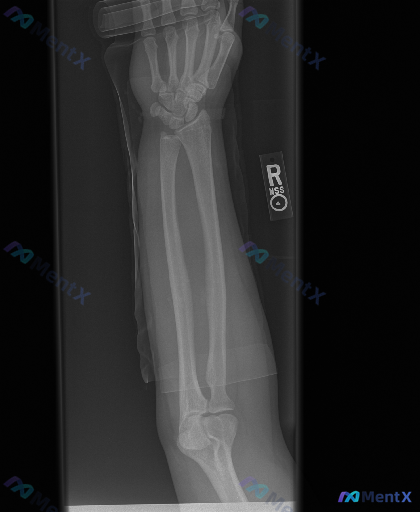

- 骨骼方面:桡骨远端干骺端区域可见骨皮质中断,远折端有向背侧/桡侧移位的迹象;尺骨茎突处也有骨皮质不连续的表现。

- 关节方面:桡腕关节的正常解剖关系似乎有改变,下尺桡关节区域看起来间隙不太规整。

- 软组织:桡骨远端周围有皮下脂肪层模糊、密度增高的表现。

- 其他:影像边缘能看到一些半透光的固定材料影。

骨质密度整体看起来尚可,没有明显的溶骨性或成骨性破坏,也看不到层状/花边状的骨膜反应;近端的肘关节在片内也没见明显脱位。